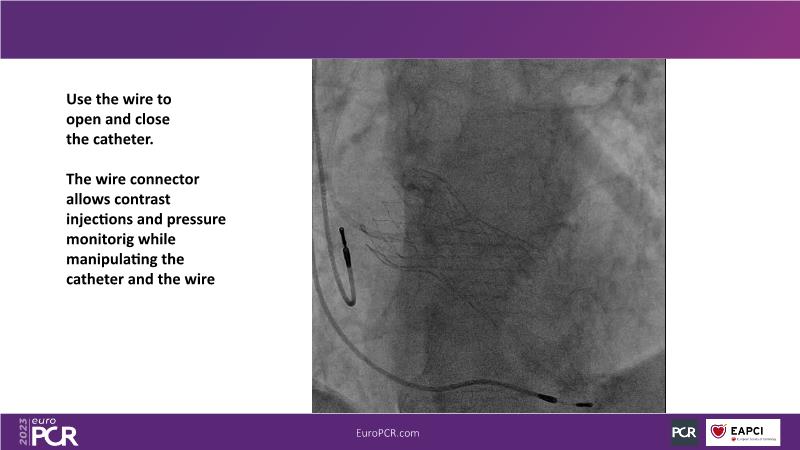

Discover the key factors to consider in selecting the optimal valve and implant technique for transcatheter aortic valve implantation (TAVI) to achieve optimal procedural outcomes. Gain insights into the impact of device choice and implantation technique on coronary access following TAVI and learn valuable strategies for tailoring your TAVI technique to complex scenarios, including bicuspid aortic valves, large and calcified anatomies, and ensuring coronary access.

- To appreciate the impact of device choice and implantation technique on coronary access after TAVI

- To learn how to tailor your TAVI technique to complex situations: bicuspid aortic valves, large, calcified anatomies and coronary access